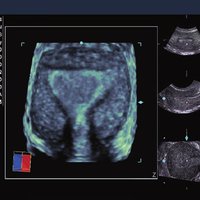

Siemens ACUSON X300 PE Beschreibung

Das Siemens Acuson X300 PE ist ein mittelklassiges Herz-Kreislauf-Ultraschallgerät mit gemeinsamen Servicefunktionen. Die Premiumedition verfügt über 4D-Technologie und eine doppelte Auswahl an Sonden; zusammen mit vielen hochwertigen Funktionen ist sie in einem mittleren Preissegment erhältlich. Das Siemens ACUSON X300 PE bietet eine Vielzahl von Lösungen, einschließlich allgemeine Bildgebung, interdisziplinäre  Dienstleistungen, OB/GYN, Kardiologie, Urologie, Endokrinologie, Notfallmedizin und viele andere fachspezifische Anwendungen.

• Features: 3D, 4D, Farb/Doppler